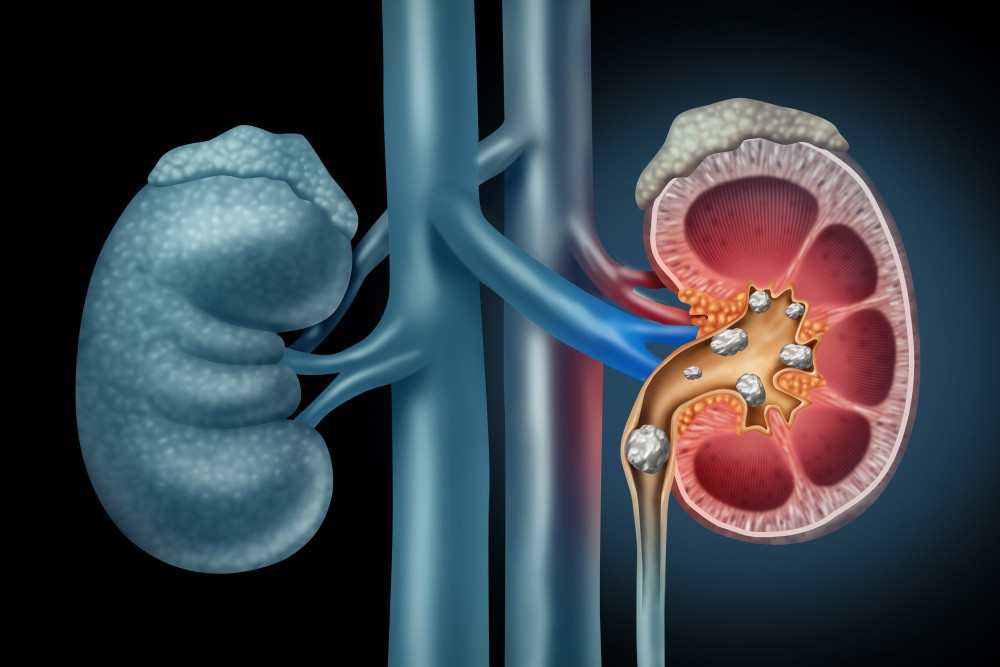

Kenali aHUS, Penyakit Langka yang Rusak Ginjal

JAKARTA – Penyakit langka sering kali tidak mendapatkan perhatian yang cukup karena jumlah penderitanya yang […]